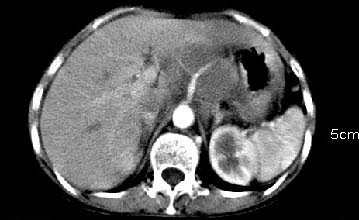

主动脉-胰腺间隙可见巨大分叶状软组织肿块影,包绕腹主动脉、腹腔干及其分支、腔静脉等大血管,增强呈无明显强化,临近脏器明显受压移位,增强示有分界。肝右叶可见局限性低密影,边缘清楚。

考虑腹膜后淋巴瘤。

肝胃之间、肝十二指肠韧带,胰头后、腹主a周围,融合而成团块状影,包绕血管[腹腔干、肠系膜上动脉,腹主动脉],胰腺前移后缘分界欠清,与肝胃分界清,肿块未见明显强化,肝右叶后段小囊肿。